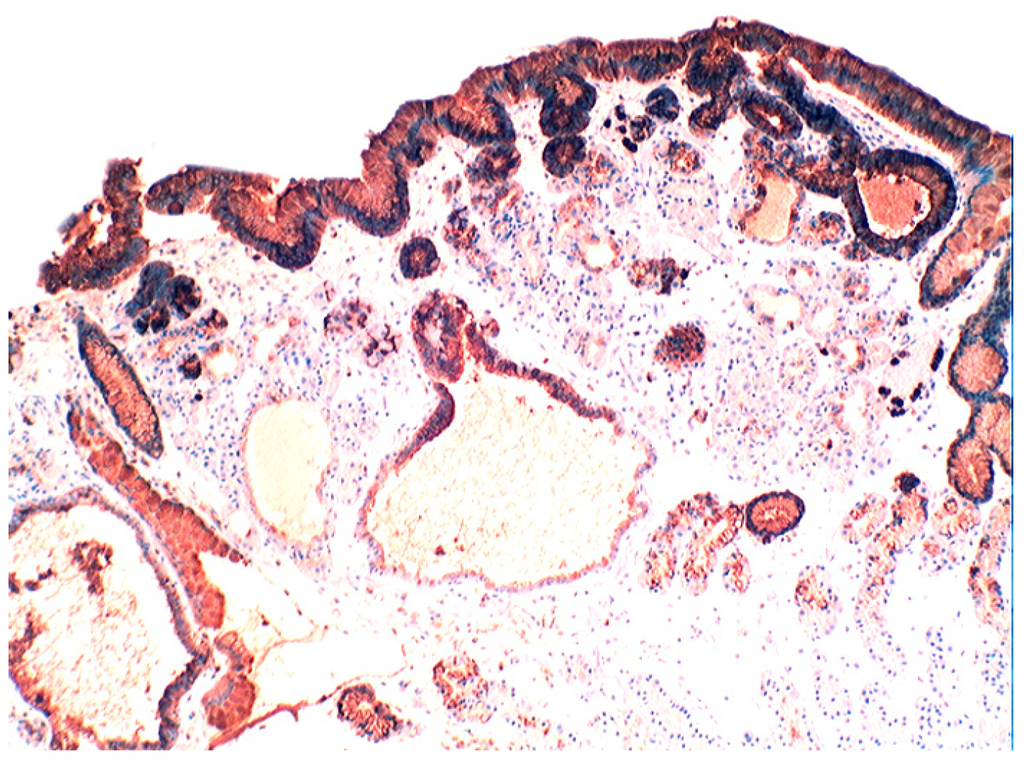

In the normal duodenal mucosa, Paneth cells produce lysozyme. In coeliac disease, lysozyme is up-regulated in goblet cells, in dilated crypts with mucus-metaplasia (Figure 9), a phenomenon more apparent in the bulbus [10] (Figure 10). It is not inconceivable that the lysozyme-rich mucus metaplasia mirror stem cell adaptation to the signals generated by the pathogenic bacteria present in the duodenal microenvironment [63].

Figure 10.

Chronic atrophic duodenitis (celiac disease). Villous atrophy showing extensive lysozyme-rich mucus metaplasia of the crypts. Note absence of Paneth cells (lysozyme immunostain, ×10).